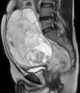

Desmoplastic small round cell tumor

Desmoplastic small-round-cell tumor (DSRCT) is an aggressive and rare cancer that primarily occurs as masses in the abdomen. Other areas affected may include the lymph nodes, the lining of the abdomen, diaphragm, spleen, liver, chest wall, skull, spinal cord, large intestine, small intestine, bladder, brain, lungs, testicles, ovaries, and the pelvis. [Source: Wikipedia ]